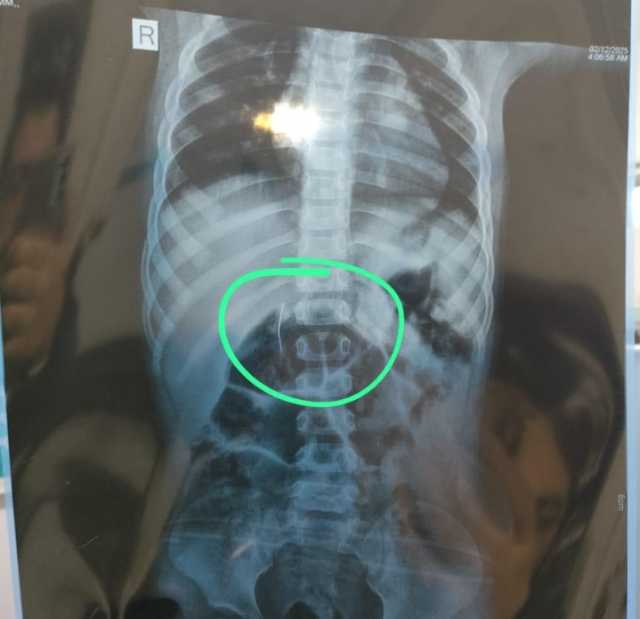

وأوضح البيلي أن الحالات الثلاث وصلت إلى المستشفى في أوقات متقاربة خلال فترات مسائية وعلى مدار يومين فقط، حيث استقبلتهم وحدة مناظير الأطفال بالتنسيق مع مركز الخدمات الطارئة بالمديرية، لافتًا إلى أن الأطفال كانوا يعانون من ابتلاع أجسام معدنية حادة وشديدة الخطورة، وهو ما ينذر بحدوث مضاعفات قد تمتد إلى النزيف أو حدوث ثقوب في الجهاز الهضمي أو تلف الأنسجة.

وأشار وكيل الوزارة إلى أن الفريق الطبي نجح أولًا في استخراج دبوس معدني مدبب من طفلة كانت معرضة لخطر ثقب المريء أو المعدة، ثم تمكن من إخراج قطعة مغناطيسية خطرة من طفل آخر قبل أن تتسبب في التصاق أجزاء من الأمعاء أو حدوث انسداد، كما قام الفريق الطبي باستخراج بطارية معدنية من طفل ثالث قبل أن تؤدي إلى تآكل شديد بجدار المريء، مؤكدًا أن التدخل السريع والمهارة الدقيقة للفريق الطبي كانا عاملين حاسمين في إنقاذ حياة الأطفال الثلاثة.

ولفت الدكتور البيلي إلى أن جميع العمليات أُجريت باستخدام المنظار ودون أي تدخل جراحي، ما سمح بخروج الأطفال بحالة صحية مستقرة تمامًا بعد الاطمئنان على سلامة أجهزتهم الداخلية، مشيدًا بكفاءة الفريق الطبي وقدرته على التعامل مع مثل هذه الحالات المعقدة في وقت قياسي، وباستخدام تقنيات متقدمة تتيح أعلى معدلات الأمان والدقة.